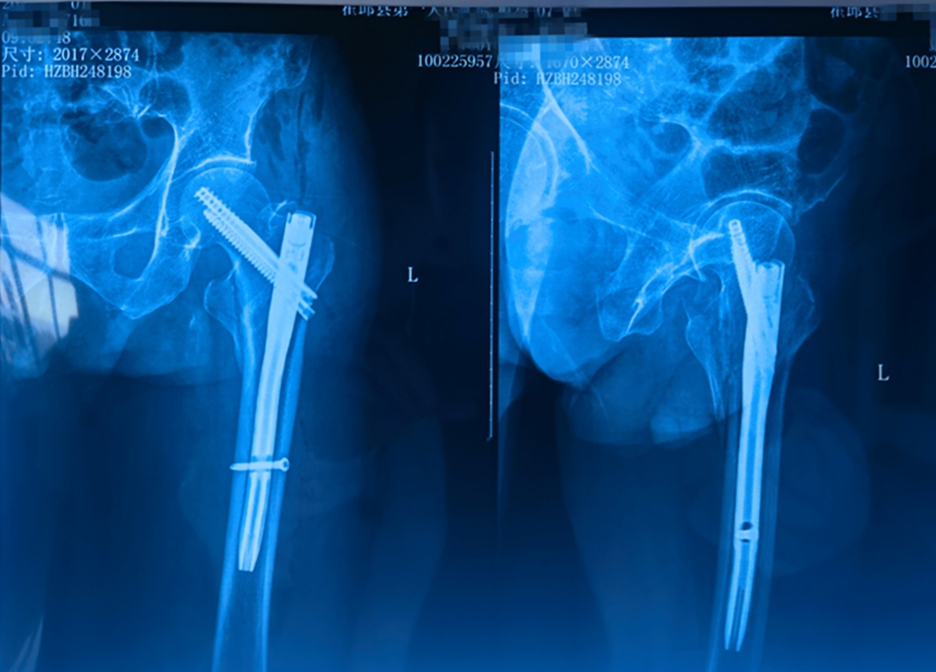

梁爷爷不慎摔倒致左股骨粗隆间骨折,术前更查出严重贫血和低蛋白血症。面对“人生最后一次骨折”的凶险与高龄挑战,骨科主任王家宁团队迎难而上。他们迅速联合输血科精准输血、输注白蛋白改善状态,筑牢手术安全基础。 同时,依托省级区域(专科)医疗中心平台,安医大二附院骨科许新忠教授亲临主刀,采用先进的“闭合复位髓内钉内固定术”(创伤小、出血少、恢复快)。团队精湛配合下,手术顺利完成。

术后精心护理下,梁爷爷恢复迅速,已能床边坐起自主进食。家属送来锦旗盛赞:“是王主任团队的专业和坚持,给了父亲重获新生的希望!”